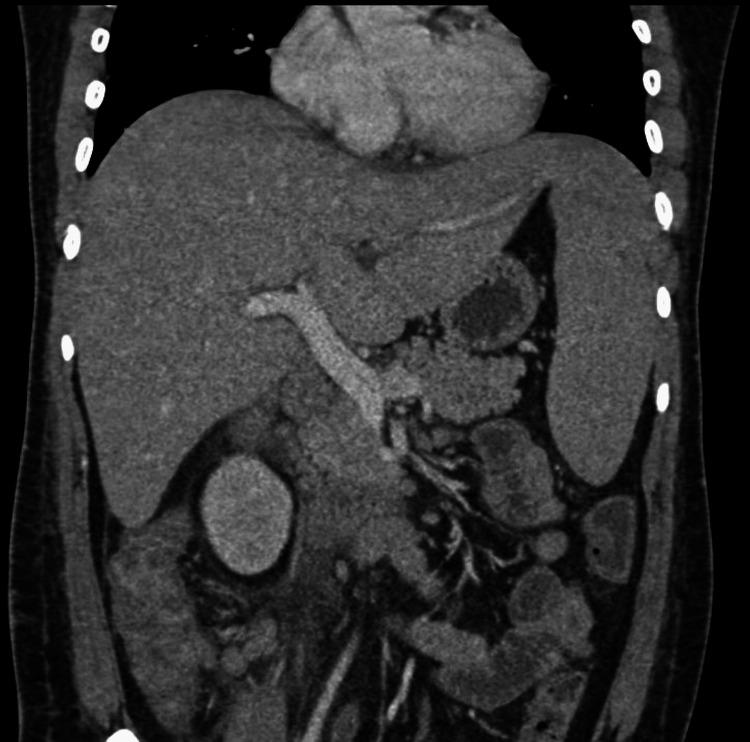

Hemophagocytic lymphohistiocytosis (HLH) is a potentially fatal hyper-inflammatory state that is caused by a highly activated but ineffective immune system. It can be primary or secondary to triggers like infections, malignancies, and autoimmune conditions. The authors present the case of a young male with a fever and abdominal pain due to typhoid. He continued to have a high-spiking fever and developed dyspnea, requiring oxygen therapy despite being treated with appropriate antibiotics. Laboratory evaluation revealed cytopenias and deranged liver function tests, and abdominal imaging revealed hepatosplenomegaly. These clinical and laboratory findings raised suspicion of HLH secondary to typhoid fever. Further investigations were suggestive of hyperferritinemia and hypofibrinogenemia, and bone marrow aspirates showed hemophagocytes. The patient was treated with immunosuppression (dexamethasone) and antibiotics and showed remarkable recovery. Hemophagocytic lymphohistiocytosis should be suspected in patients with tropical infections like enteric fever, tuberculosis, malaria, dengue, etc. that worsen despite appropriate treatment, as late diagnosis is associated with greater mortality.

噬血细胞性淋巴组织细胞增生症(HLH)是一种潜在致命的高炎症状态,由高度激活但无效的免疫系统引起。它可以是原发性的,也可以继发于感染、恶性肿瘤和自身免疫性疾病等触发因素。作者介绍了一例因伤寒出现发热和腹痛的年轻男性病例。尽管接受了适当的抗生素治疗,他仍持续高热,并出现呼吸困难,需要吸氧治疗。实验室检查发现血细胞减少和肝功能检查异常,腹部影像学检查显示肝脾肿大。这些临床和实验室检查结果引起了对伤寒继发HLH的怀疑。进一步检查提示高铁蛋白血症和低纤维蛋白原血症,骨髓穿刺显示有噬血细胞。该患者接受了免疫抑制治疗(地塞米松)和抗生素治疗,病情显著好转。对于患有伤寒热、结核病、疟疾、登革热等热带感染且尽管接受了适当治疗仍病情恶化的患者,应怀疑噬血细胞性淋巴组织细胞增生症,因为延迟诊断与更高的死亡率相关。